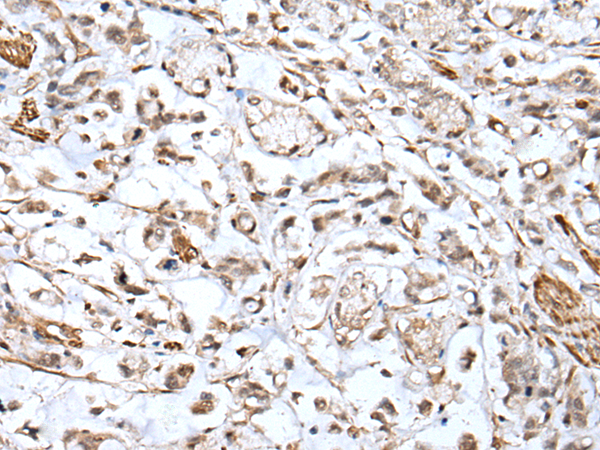

IHC positive control: |

Human cervical cancer and human gastric cancer |

IHC Recommend dilution: |

25-100 |